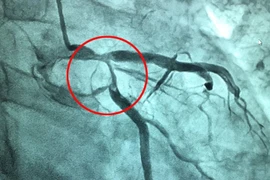

Cơn đau thắt ngực không ổn định xuất hiện do sự giảm đột ngột của dòng máu mạch vành nuôi cơ tim, có thể dẫn đến nhồi máu cơ tim và đe dọa tính mạng bệnh nhân nếu không được cấp cứu kịp thời.

(khoahocdoisong.vn) - Kỹ thuật dùng một loại ống thông nhỏ (catheter) để đưa một bóng nhỏ vào lòng động mạch vành bị tắc rồi nong và đặt Stent (giá đỡ) để làm tái thông dòng máu.